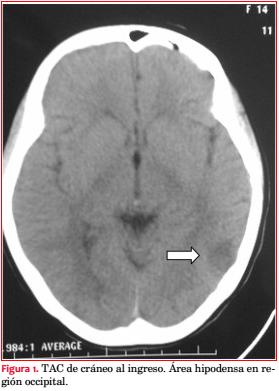

Un día después se registran cifras elevadas de PA, hasta 150/100 mmHg. Se inicia tratamiento con alfa-metildopa 500 mg cada 8 horas, y amlodipina 5 mg cada 12 horas, estabilizándose la PA en 120/90 mmHg. Al día siguiente instala cefaleas, con PA 130/90 mmHg y reitera convulsión tónico-clónica generalizada, debiendo recibir diazepam intravenoso para yugular la crisis. Se reinstala carga e infusión continua de sulfato de Mg. Evoluciona con cefaleas, amaurosis, parestesias y paresia de miembro superior izquierdo (MSI). Se realiza TAC de cráneo que evidencia área hipodensa córtico subcortical occipital, compatible con SLEPR (figura 1), y en el mismo acto angio-TAC, no observándose trombosis de senos venosos. El electroencefalograma (EEG) mostró sufrimiento encefálico difuso, con actividad paroxística focal derecha, en regiones central y temporal. Se continuó con la medicación antihipertensiva, manteniendo valores de PA sistólica de 90-100 mmHg, cediendo la cefalea, y retrocediendo toda la sintomatología neurológica.

Las manifestaciones neurológicas, amaurosis bilateral, parestesias y paresia de MSI permitieron hacer el diagnóstico clínico de SLEPR, que se confirmó con la TAC de cráneo por la presencia de áreas hipodensas corticales occipitales que revirtieron completamente en el control posterior. Estas imágenes evidenciaron edema cerebral vasogénico. El diagnóstico de SLEPR es clínico-radiológico (resonancia magnética/tomografía computada), obteniéndose imágenes de edema vasogénico simétrico bilateral en territorio de la circulación cerebral posterior con distribución preferente en la sustancia blanca subcortical y frecuente en lóbulo parietal y occipital en 98% de los casos(12). El edema cerebral se explica por mecanismos patogénicos no excluyentes, la encefalopatía hipertensiva y la disfunción endotelial. Se observa en diferentes situaciones clínicas, siendo el precipitante común un aumento brusco de la PA(13). Existen condiciones asociadas a SLEPR, como sepsis, enfermedades autoinmunes (lupus eritematoso sistémico), o síndrome antifosfolipídico, que fueron descartadas en esta paciente.